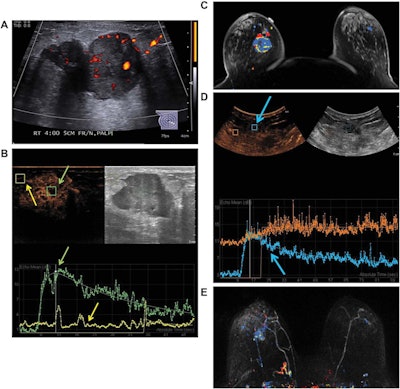

Images are from a 50-year-old woman presenting with a right breast lump that has biopsy-proven infiltrating ductal carcinoma. A: Targeted right-breast ultrasound imaging showed an oval hypoechoic mass with indistinct margins measuring up to 3.7 cm. B: At baseline before starting neoadjuvant chemotherapy, CEUS showed an avidly enhancing tumor (green arrows) with tumor peak intensity on the time-intensity curve generated by the Qlab software. The region of interest was placed on adjacent normal breast tissue (yellow arrows), which had a flat line on the time-intensity curve. The y-axis of the time-intensity graph corresponds to the intensity or mean echo (decibels), whereas the x-axis corresponds to the absolute time (seconds). C: Axial postcontrast fat-saturated MRI at baseline showed an enhancing tumor with mixed kinetics in the right breast. After neoadjuvant chemotherapy was completed but before surgery, contrast-enhanced and MRI scans were again performed. D: CEUS showed a 2-cm residual enhancing tumor with a time-intensity curve (blue arrows) that had rapid enhancement and washout. E: Maximum-intensity projection contrast-enhanced MRI performed after neoadjuvant chemotherapy was completed showed a decrease in the size of tumor to 2 cm with predominantly progressive kinetics. At the time of right lumpectomy, this patient had 1.5 cm of invasive tumor in the right breast, consistent with a noncomplete pathologic response. Both the contrast-enhanced ultrasound and MRI studies predicted that there would be noncomplete pathologic response at the time of surgery. Images courtesy of the Journal of Ultrasound in Medicine.

At baseline prior to treatment, contrast ultrasound and MRI both yielded a 3.1-cm median tumor size; the modalities had strong correlation (r = 0.88, p < 0.001) in tumor size measurements. The researchers noted that one patient had a deep tumor that did not enhance on baseline CEUS, but it was visible on conventional ultrasound and displayed subthreshold enhancement on MRI.

After neoadjuvant chemotherapy, agreement on tumor size dropped (r = 0.66, p = 0.004) but was still comparable. The researchers observed, however, that in a subset of 15 patients who had both CEUS and MRI studies that could be compared with tumor size at surgery, CEUS (r = 0.75, p < 0.001) correlated better with tumor size at surgery than MRI did (r = 0.42, p = 0.095).

In addition, contrast ultrasound and MRI were equally effective in predicting pathologic response to treatment. The modalities both accurately predicted three (75%) of the four patients who had a complete pathologic response, and eight (72.7%) of the 11 patients with a noncomplete pathological response.